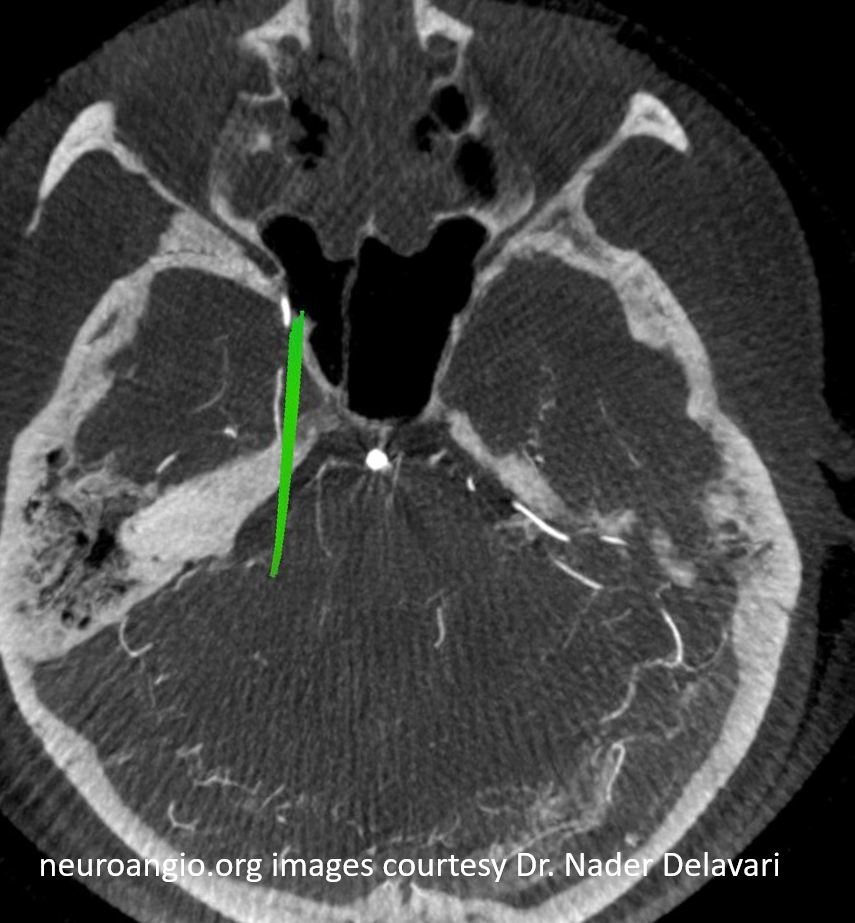

And, in case you really dont believe its the trigeminal artery, check out these co-registration images of angio (axial MIP reconstructions of rotational angio) and finally with superimposed tractography of the Vth nerve! Images courtesy Dr. Nader Delavari

Superimposed MRI and angio axials (our trigeminal artery is shown bi arrow)

Now with tractography of CN V